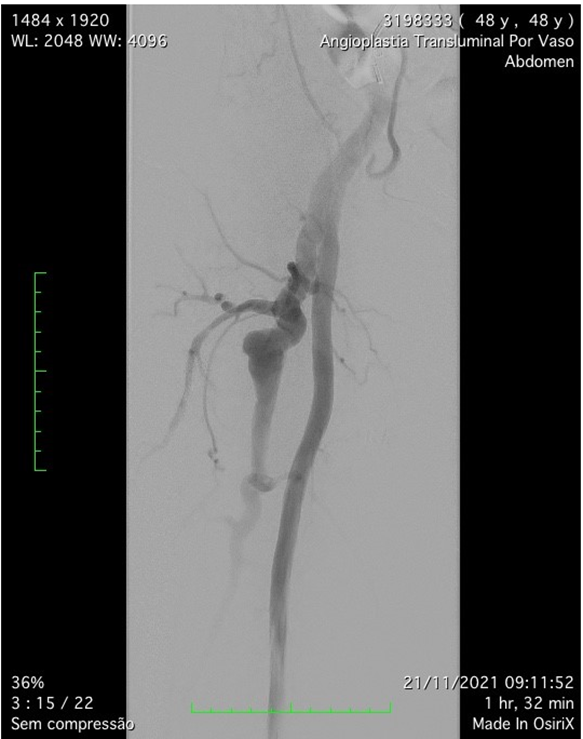

Figure 3: Preoperative arteriography confirming Deep femoral artery aneurysm.

The patient was scheduled to undergo endovascular treatment of the deep femoral artery aneurysm. Under general anesthesia, a left common femoral artery was punctured guided with a duplex ultrasound., with a 6f 11cm sheath. We decided to use a contralateral access and perform the whole intervention percutaneously. After the puncture, the Perclose Proglide â was inserted, in order to preload and guarantee the sealing of the puncture. Then, a 0,035”260cm Terumo â was passed untiused to perform the crossing overl of the aorta, and a 9F 11cm sheath was placed through the left common femoral artery. The patient was heparinized with 5000UI intravenous in bolus., and the aorta was crossed with an internal mammary 6F catheter alongside the 0,035”260cm Terumo â. We performed a right limb arteriography to confirm the deep femoral artery aneurysm (Figure 3s 5 and 6). The deep femoral artery was properly catheterizedselected with a Headhunter catheter 5F. After this, and we changed the guidewire for an Amplatz 0,035”260cm, in order to place a 55cm 9F delivery system catheter until the origin of the right deep femoral artery. In the arteriography, we have identified a larger branch emerging from the first portion of the deep femoral artery, and we have decided to embolize this branch, to avoid endoleak type II, since it was a larger branch. The microcatheter Progreat â 2,7F alongside the microguidewire Avigo â was used to select the branch. We embolized this branch with Azur â coils 2 4x5, 6x10, 6x15 and 6x20 (figures 7 and 8). After the successful embolization, a covered self-expandable 9x100 Solaris â (Scitech Medical, Brasil) was placed under roadmap into the proximal and distal deep femoral artery aneurysm, and post dilatated with a 9x80 catheter balloon Oceanus â (figure 4 Figures 9 and 10). There were no endoleaks, and the deep femoral artery patency was identified. All the materials were removed, and we completed the final step of the perclose Proglide â puncture closing. The patient was transferred to the room, being discharged from the hospital two days after the surgery with no complications, femoral, popliteal and podal pulses present bilaterally, taking Aspirin 100mg / day and Clopidogrel 75mg/day. After 1 month the patient was evaluated, presenting no further symptoms, no palpable mass in the right groin, and was submitted to a Duplex Ultrasound (Figure 5s 11 and 12), that showed deep femoral artery patency, stent patency, reduction of the aneurysm sac and no endoleaks. Furthermore, after one year follow-up, the patient remained assymptomatic, with Duplex Ultrasound showing deep femoral and stent patency and no endoleaks. (Figure 6).